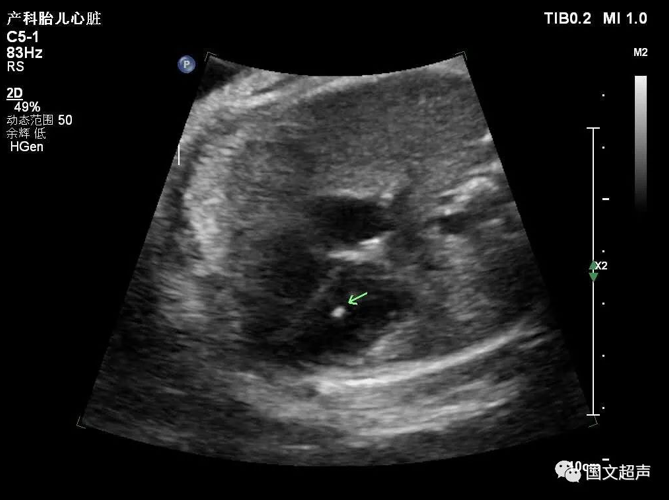

三.關于心室強回聲光點

胎兒心室內強回聲光點不是一種心臟畸形,它只是一個聲像圖表現,是胎兒染色體異常的一種潛在體現,也被稱為超聲軟指標(不是器質的異常,其他的軟指標還有NT增寬、腎盂分離、側腦室增寬、腸管回聲增強、四肢長骨短、鼻骨短小等等)。

大部分強回聲光點隨孕周增加而縮小,回聲強度也逐漸減弱。到足月妊娠幾乎完全消失,少數則可一直存在,直至分娩,甚至產后超聲仍能觀察到。